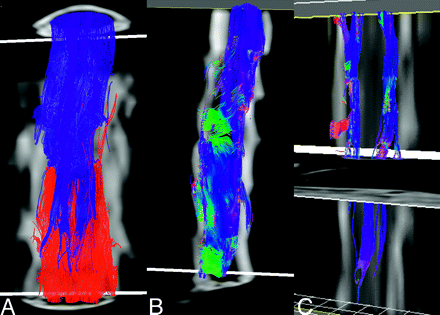

Fiber tracking results representative of a healthy adult obtained using the optimized trigger timing detailed above are shown in Fig 5. When the ROI contains the entire cross-section of the spinal cord in the most superior (or inferior) section, it is notable that relatively few fibers extend from end to end of the comparatively short imaging volume (typically 2-3 vertebral bodies in the current implementation). At least part of this attrition appears to be due to fiber convergence and crossing at the emergence of nerve roots (Fig 5B). In light of the residual errors in the eigenvectors seen in Fig 4, however, one cannot rule out the presence of artifactual attrition as well. By limiting the initial ROI to the lateral white matter in the most superior section, a subset of the tracks can be more clearly seen. These tracks remain lateralized, and with a suitable stopping threshold, the depicted fibers do not appear to enter the central gray matter of the spinal cord. Blue in Fig 5B, -C, depicts the cranial-caudal orientation of the local first eigenvector, so the dominant direction of diffusion is readily apparent. Intermittent zones of green and red correspond to the origins and progressions of nerve roots.

Fiber-tracking results from a healthy control (A) with the entire cross-section of the spinal cord in both the superior (blue fibers) and inferior section (red fibers) used as seeding regions. Few tracks extend from end to end of the scan volume (covering slightly more than 2 vertebral bodies). Color coding the same fibers in accordance with local orientation of the first eigenvector (blue, rostral-caudal; red, left-right; green, anteroposterior), many of the fibers appear to converge on an emerging nerve root, suggesting that fiber crossing may be present. Restricting seeding to the lateral white matter in the in the most superior section (C) shows no penetration of these tracks into the central regions of the cord.